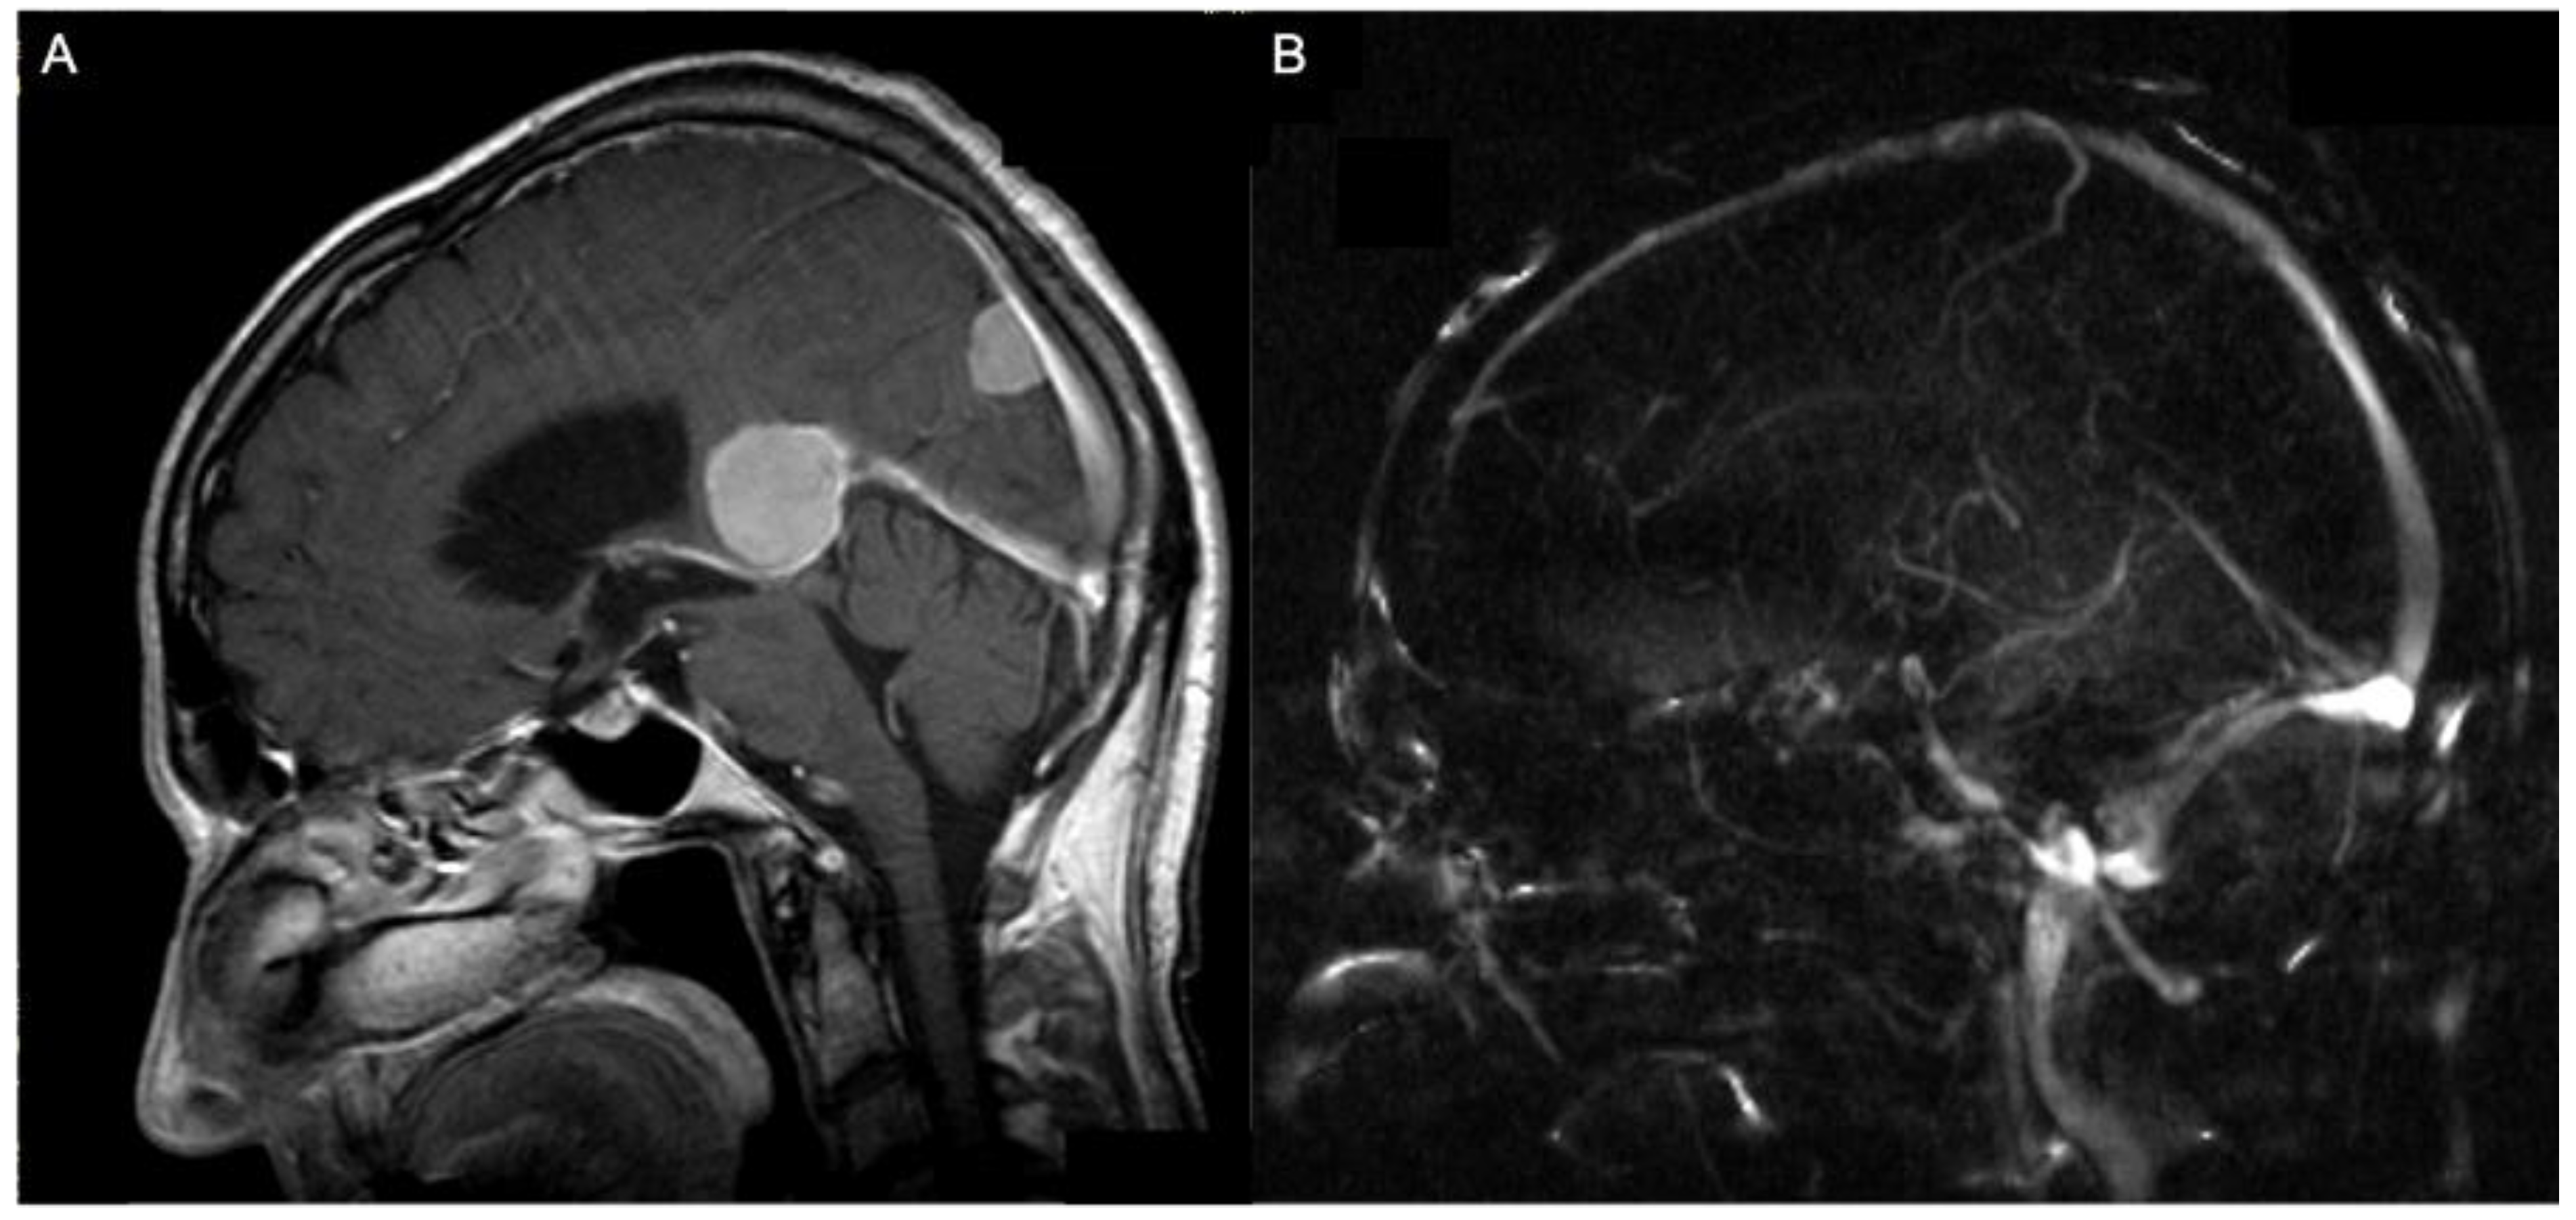

2.2. Volumetric Analysis, Vascular Features, and Tentorial Angle

3.2. Preoperative Imaging Data

| Tentorial angle | 49.6 (±6.2) | |